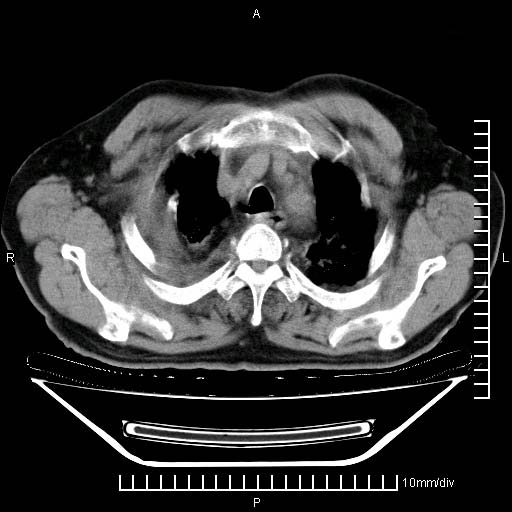

既往肺结核,近10几天,咳嗽,咳痰,右侧胸痛,疼痛较明显,右上肺斑块考虑结核灶胸膜粘连,增强,可惜动脉期没有定好,未见强化,可延迟4分后又见较明显强化,中心见低密度影,如果说结核是边缘强化,可这个灶强化的面积挺大的,让人很挠头。

1)两肺继发性肺结核。2)右侧胸膜增厚+少量胸腔积液。